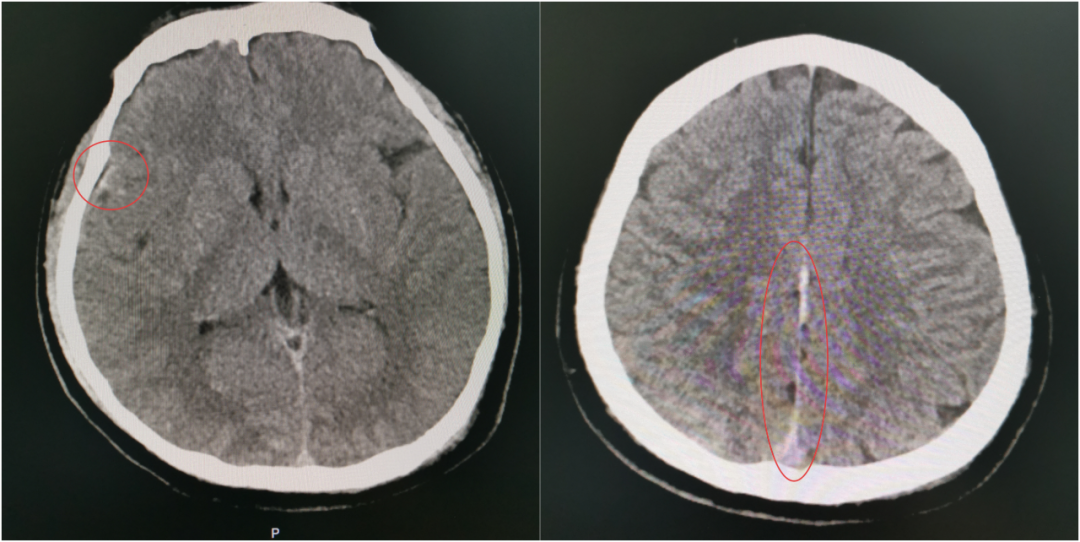

小徐颅脑内部存在多处出血点,枕骨破裂

争分夺秒,必须环环紧扣。完成必要指标监测后,立即将小徐送往放射科,10分钟内完成急诊CT检查。结果显示:枕骨破裂,蛛网膜下腔出血。

当第二次 CT 提示出现硬膜外血肿、蛛网膜下腔出血范围进一步扩大时,虽然符合预判,但每个人都清楚:出血量和点位的不可控,血肿扩大可能压迫脑组织,任何微小变化都可能改写结局,之前的一系列努力可能功亏一篑。

伤情再次变化,出血范围扩大